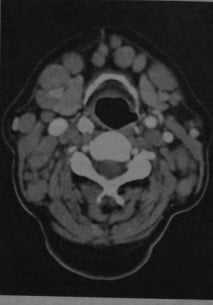

Неходжкинская лимфома. КТ с контрастированием: множественные лимфатические узлы под нижней челюстью и около яремной вены, а также позади грудино-ключично-сосцевидной мышцы. Узлы имеют овальную или округлую форму, повышенную плотность по сравнению с окружающими мышцами, после введения контраста наблюдается гомогенное усиление.